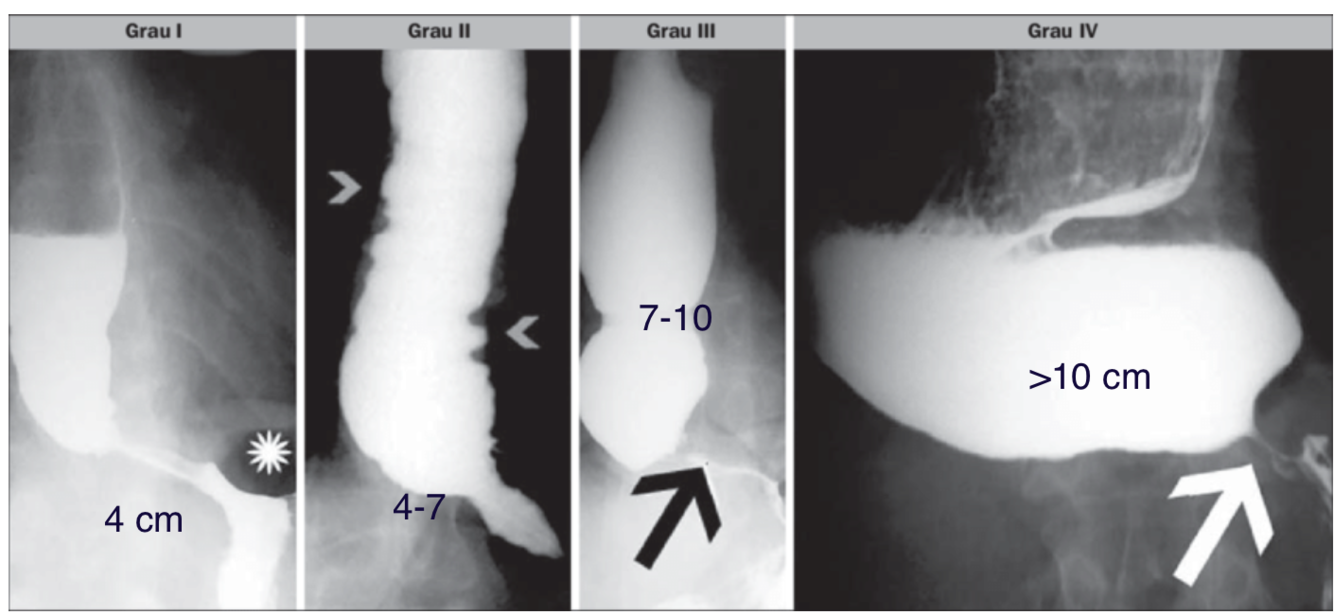

Rezende e Moreira: megaesôfago

(asterisco): presença de bolha gástrica

(cabeças de setas): ondas terciárias frequentes

(seta): aspecto de “ bico de pássaro “ da cárdia